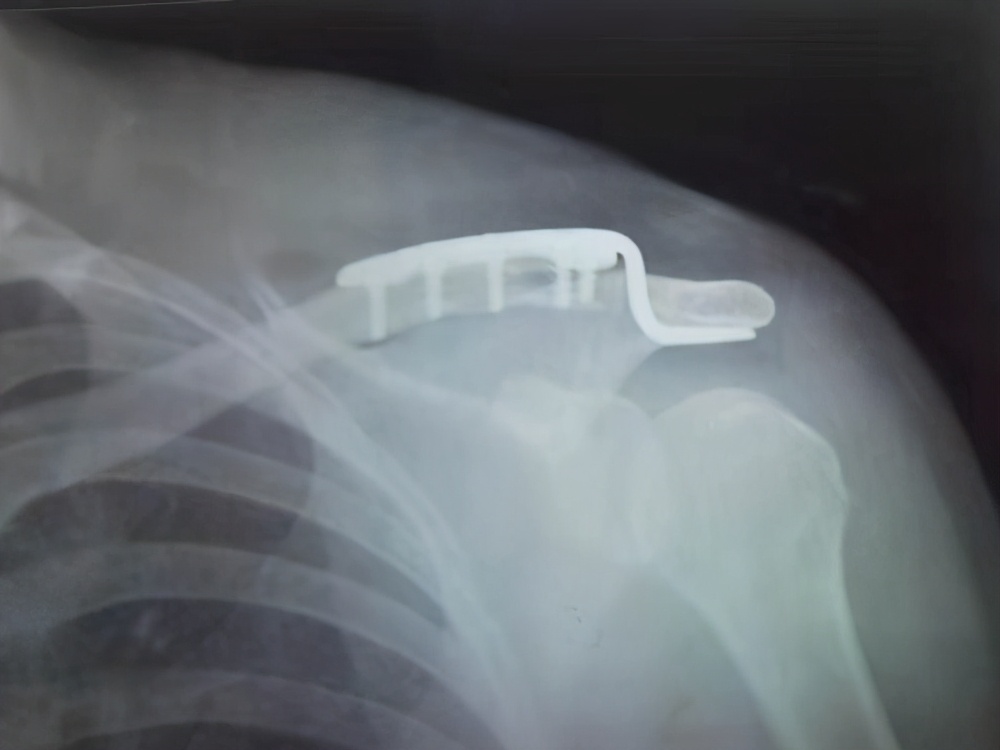

3、影响到功能了:我骨折愈合了,但是由于钢板的原因导致我一些功能的丧失,比如 锁骨钩钢板,这是带钩的钢板,不同于那些直钢板,有的人 会在抬胳膊的时候感觉钢板在撞击我的肩膀,这个时候那就要尽量取掉了;建议6-8个月来取,足踝关节部位的钢板,如果踝关节的功能受到影响,建议取出。

锁骨钩钢板